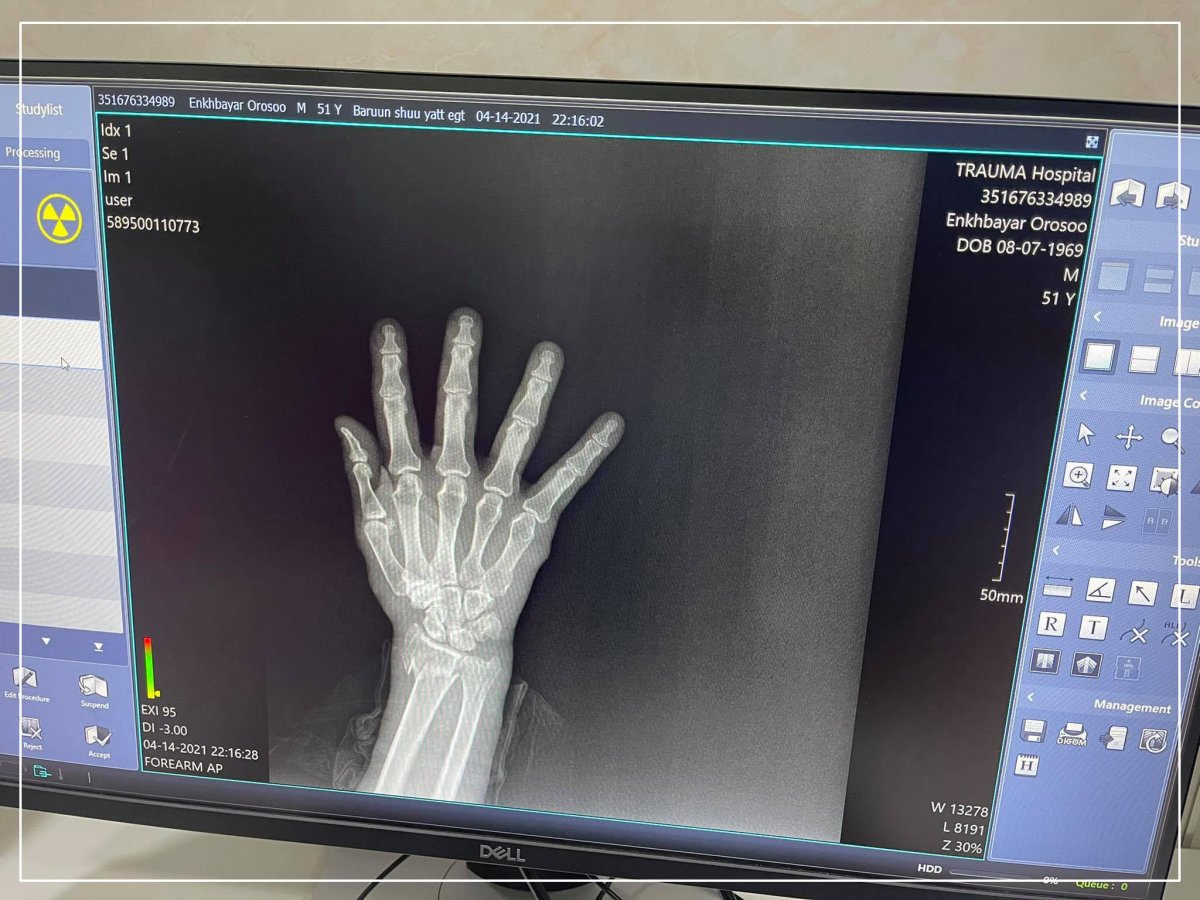

ГССҮТ сүүлийн дижитал рентген аппаратаар бүтэн биеийн рентген зураг авах боломжтой боллоо

Гэмтэл согог судлалын үндэсний төвийн Дүрс оношилгооны тасаг нь Хүлээн авах яаралтай тусламжийн хэсэгтээ Эрүүл мэндийн яамны санхүүжилтээр Япон улсад үйлдвэрлэсэн хитачи брендийн 2021 онд үйлдвэрлэгдсэн Раднекс-50 загварын бүтэн дижитал рентген аппарат суурилуулсан байна.

Уг аппарат ашиглалтад орсноор жилд 100 мянгаас дээш зураг авах бөгөөд 24 цагийн турш үйлчлүүлэгчийг хүлээлгэлгүй, хүндрэл учруулахааргүй ажиллах боломж бүрдүүллээ.